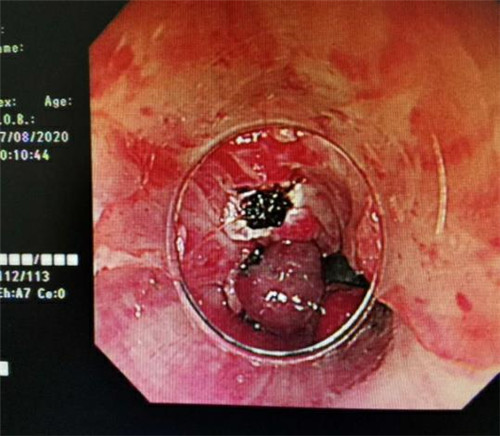

手术中,在镜下发现数条食管静脉曲张延伸至胃底,胃腔内有大量新鲜红色血液及血凝块,寻找到出血部位时仍在向外渗血,血压持续下降,患者时刻有生命危险。曹鹏副主任当机立断对曲张静脉破口处进行组织粘合剂及硬化剂注射,并对曲张静脉进行套扎治疗,在麻醉师陈琦的保驾护航下,整个过程不到半个小时,为患者成功止血,患者转危为安。

消化内镜曹鹏副主任提示广大患者,如患有肝病,需重视食管胃底静脉曲张破裂出血的原因,定期进行胃镜检查。此种疾病主要原因是肝硬化导致门脉高压,出现食管、胃底静脉曲张。当重度的静脉曲张,病人发生腹压增高如用力活动或者吃烫食、硬的食物,曲张静脉就会被划破或者自身发生破裂而导致大出血,危机生命。发生这样的情况,应第一时间拨打120到医院就诊。目前MILAN.COM可行急诊内镜检查及内镜下止血治疗。